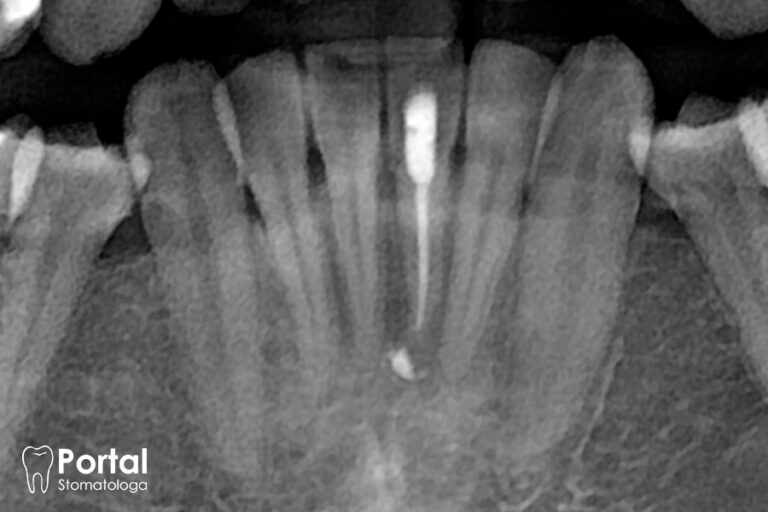

Leczenie kanałowe jest jednym z najbardziej demonizowanych zabiegów w stomatologii. Wynika to głównie z mitów utrwalonych wiele lat temu, gdy technologie były znacznie mniej zaawansowane, a znieczulenia mniej skuteczne. Dziś sytuacja wygląda zupełnie inaczej. Nowoczesne leczenie kanałowe wykonuje się w znieczuleniu miejscowym, dzięki czemu pacjent nie odczuwa bólu – jedynie niewielkie wibracje lub ucisk. Stomatolodzy korzystają z mikroskopów zabiegowych, narzędzi maszynowych i endometrów, które pozwalają na niezwykle precyzyjną pracę. Cały proces przebiega szybciej, skuteczniej i przede wszystkim komfortowo. Gabinet dentystyczny Opole stosuje techniki minimalnie inwazyjne, które pozwalają ochronić jak najwięcej zdrowych tkanek. Wszystko to sprawia, że leczenie kanałowe nie musi wiązać się ze stresem – wręcz przeciwnie, jest jedną z bardziej przewidywalnych procedur.

- Mikroskop stomatologiczny – dzięki dużemu powiększeniu lekarz widzi dużo więcej niż gołym okiem, co jest kluczowe zwłaszcza w leczeniu kanałowym i stomatologii zachowawczej.

- Cyfrowa diagnostyka i planowanie leczenia – CBCT, RTG 3D, skanery wewnątrzustne i kamery cyfrowe pozwalają precyzyjnie zaplanować każdy etap terapii, minimalizując ryzyko błędów.